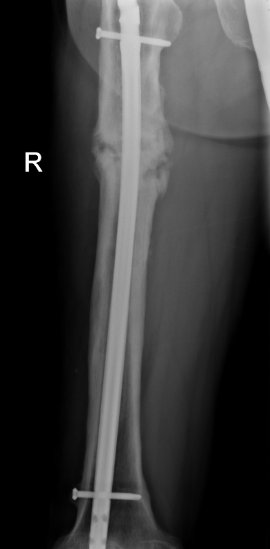

What is the diagnosis? What finding on the AP view confirms this?

L2 burst fracture Widening of interpedicle distance | indicates posterior element fracture

49

Is this injury stable or unstable? What is the appropriate follow-up?

Unstable Emergency transport | 2-3 columns of Denis involved